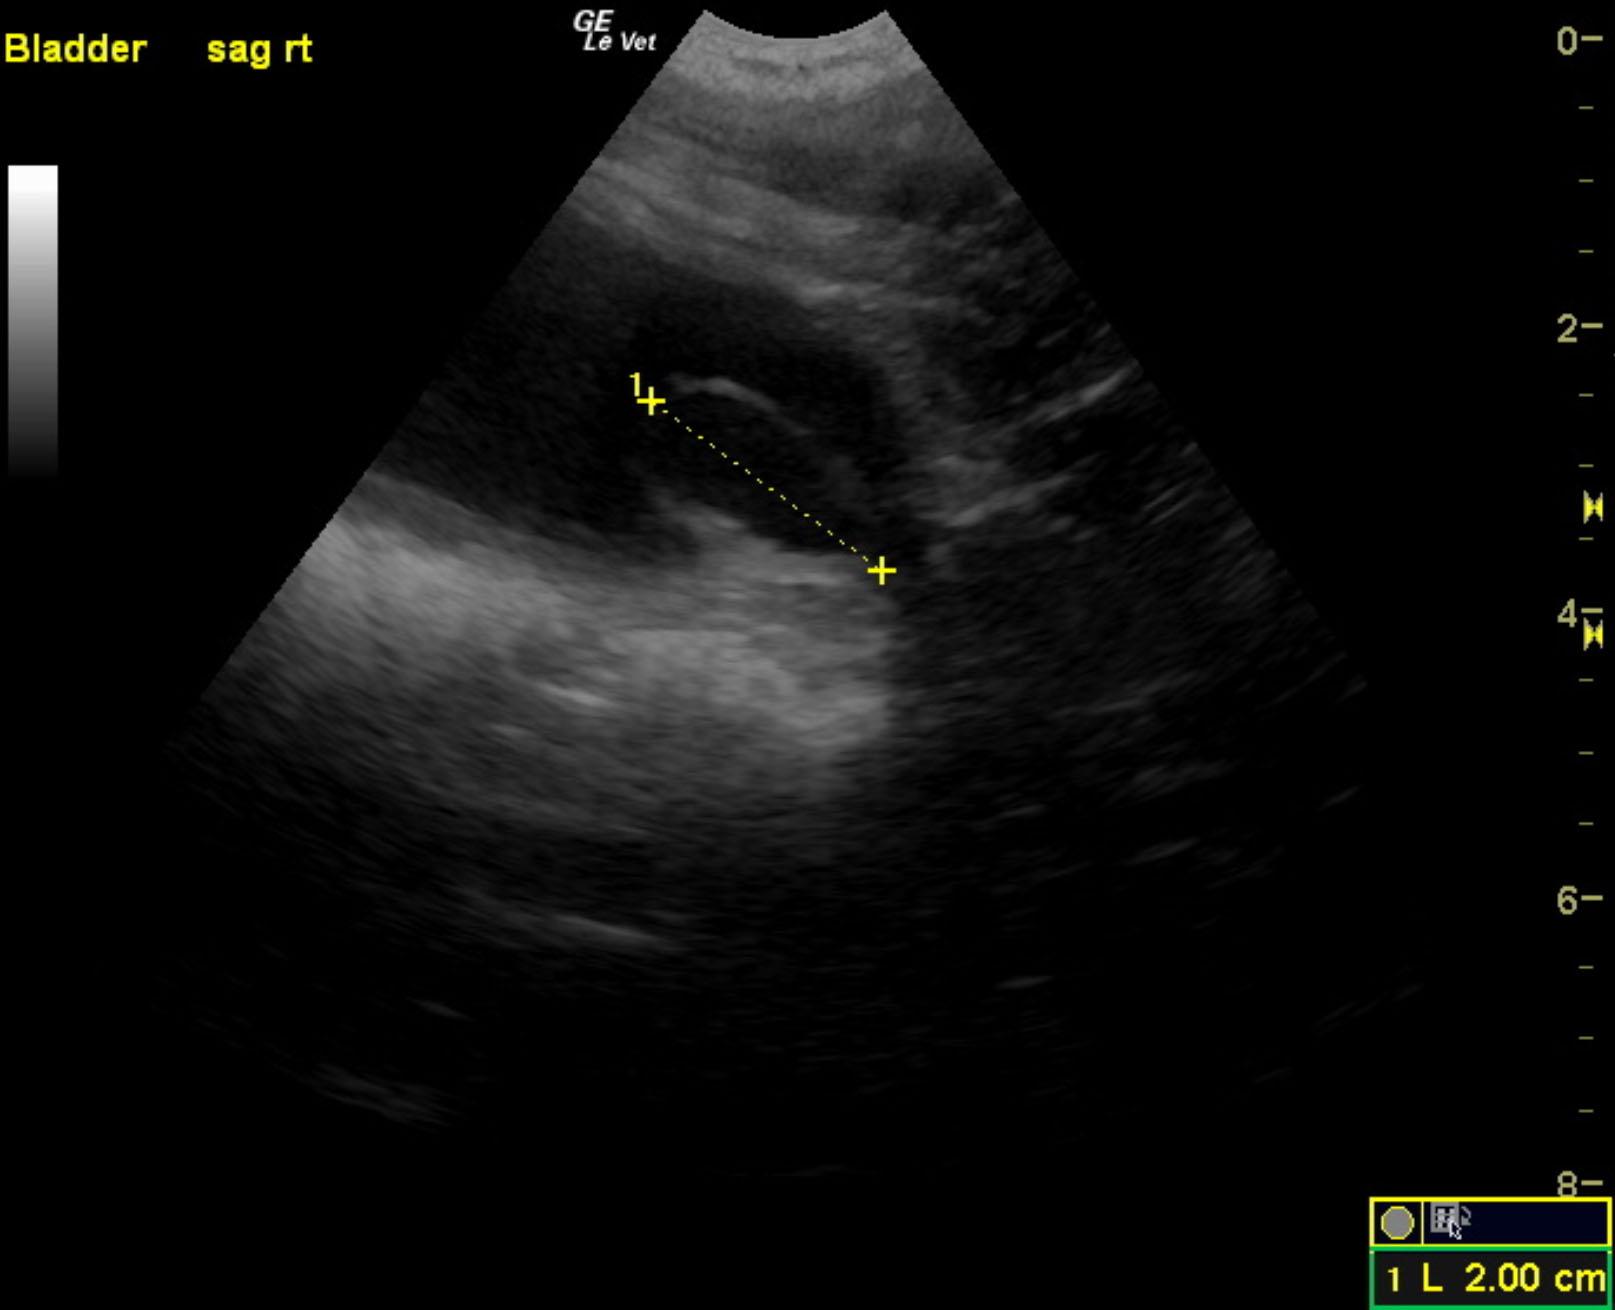

A 3-year-old neutered male Labrador Retriever dog was presented for evaluation of decreased appetite, possible polyuria and polydypsia, taking longer to urinate than normal, and hematuria. On urinalysis, isosthenuria (1.016), 3+ protein, white blood cells, and red blood cells were present. Stress leukogram was evident on CBC, but serum chemistry was within normal limits.

A 3-year-old neutered male Labrador Retriever dog was presented for evaluation of decreased appetite, possible polyuria and polydypsia, taking longer to urinate than normal, and hematuria. On urinalysis, isosthenuria (1.016), 3+ protein, white blood cells, and red blood cells were present. Stress leukogram was evident on CBC, but serum chemistry was within normal limits.